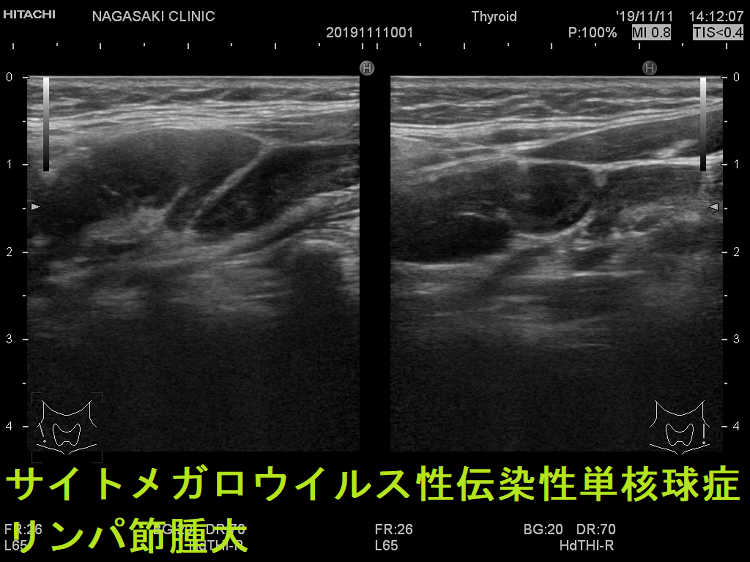

- 痛みを伴う著明な後頸部リンパ節腫脹は1〜2週頃がピークで、耳下腺の下、外側頚部まで累々と広がり、全身のリンパ節も腫大します。

- 亜急性甲状腺炎と鑑別を要する伝染性単核球症を発症